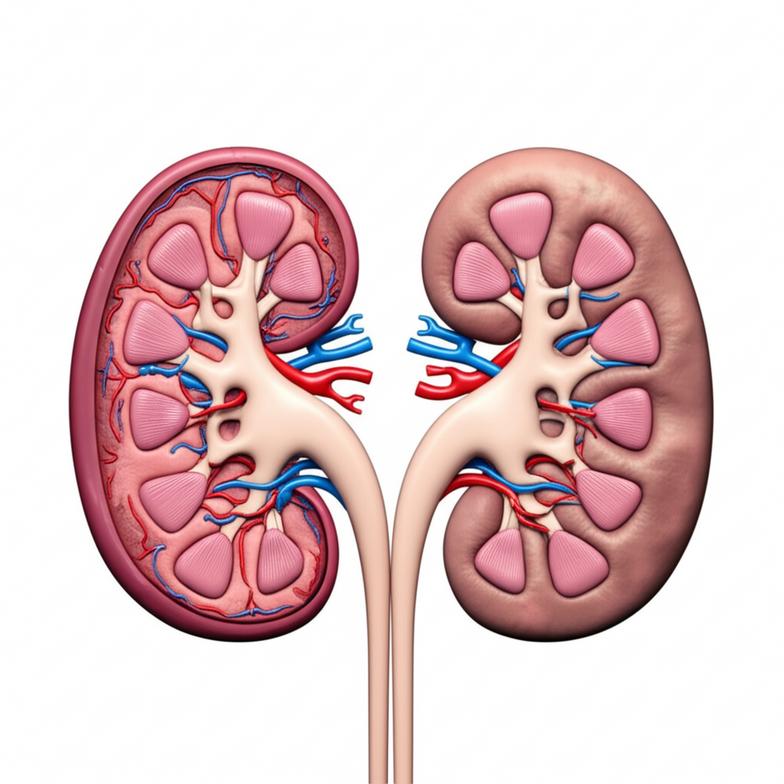

กลไกการทำงานของไตและการเสื่อมสภาพตามวัย

ไตเป็นอวัยวะสำคัญที่มีบทบาทอย่างยิ่งต่อการรักษาสมดุลของร่างกาย ไม่ใช่แค่การกรองของเสีย แต่ยังควบคุมความดันโลหิต สร้างฮอร์โมน และรักษาสมดุลของเกลือแร่ เมื่ออายุมากขึ้นหรือเมื่อร่างกายเผชิญกับปัจจัยเสี่ยงต่างๆ ความสามารถในการทำงานของไตจะค่อยๆ ลดลง ซึ่งเป็นกระบวนการที่เรียกว่า “ไตเสื่อม”

การทำความเข้าใจกลไกเหล่านี้เป็นสิ่งสำคัญเพื่อที่เราจะสามารถเข้าถึงการดูแลไตได้อย่างถูกต้องและเหมาะสม.